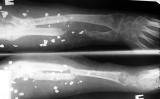

Огнестрельный дефект предплечья |

Травма год назад - огнестрельное ранение. Лечилась в ЦРБ - хирургическая обработка и фиксация предплечья в аппарате Илизарова - фиксационный вариант. Впевые обратилась к нам в сентябре 2005г.

На рентгенограммах приведены картинки - одна без вмешательств, другая в условиях ручной тракции по

оси предплечья. Кисть была полностью нефункциональна - сгибательные контрактуры

всех пальцев, выраженный отек кисти, Было решено, что тактику лечения определим после

попытки восстановления функции кисти. На сегодня - полное восстановоение объема движений в пальцах за исключением активного отведения 1 пальца. Больная даже вяжет на спицах. Больная не очень дисциплинирована, выписывалась из стационара за алкогольные радости, длительное лечение с использованием ЧКДОС мало реально.